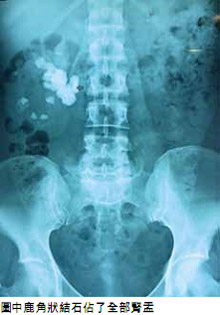

什麼是鹿角形石?

鹿角狀結石是一種非常大的鳥 糞石,它佔據了腎臟的大部分 面積,看起來像鹿角,因此被 命名為鹿角形石。由於它只會 引起輕微的疼痛或者甚至無痛, 因而大多數的情況下被忽略了 從而造成了對腎臟的損傷。